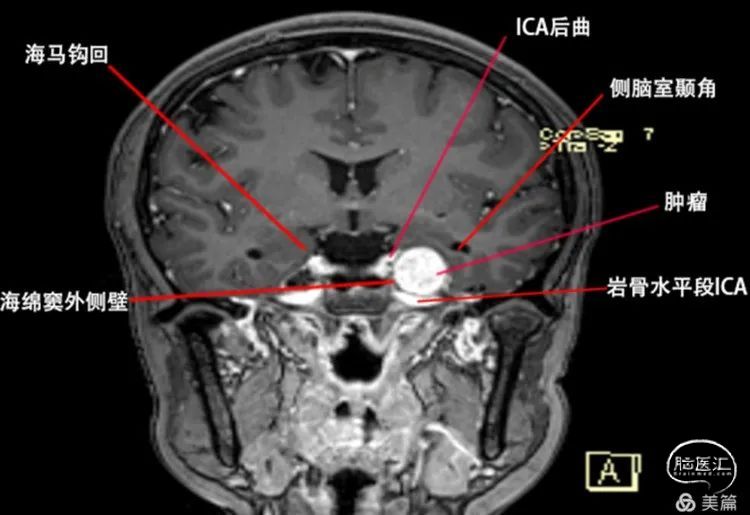

首先我们明确一个观点就是鞍旁间隙和海绵窦的关系,鞍旁间隙的范围是从眶上裂的外侧端→圆孔的外侧端→卵圆孔的外侧端→三叉神经门的外侧端→三叉神经门的内侧端,向上延续为前后岩床韧带交点,再到后床突→鞍结节的外侧端→颈内动脉近环和远环→前床突→眶上裂的外侧端。从三叉神经门的内侧端向下到外展神经的硬膜端入口→后床突最后再回到眶上裂的外侧端,这些范围区间的硬膜结构叫鞍旁间隙,而在鞍旁间隙中的一些脏壁二层硬膜之间是分开,容纳了静脉窦,这些静脉窦叫做海绵窦。所以严格意义上来说Meckel腔是鞍旁间隙的结构。Meckel腔分为前壁和后壁,其中前壁是有两层脏层硬膜形成,而后壁是由一层脏层(海绵窦的外侧壁)和一层壁层硬膜(颅骨的骨膜)形成,所以Meckel腔实际是有四层硬膜构成。此例病例肿瘤位于Meckel的前后壁之间,其内侧有颈内动脉后垂直段,其后方是岩骨的三叉神经压迹,由颞骨CT可知三叉神经N压迹处骨质受压变薄,肿瘤已经有少许突破三叉神经门的迹象,由此可以大胆的推测肿瘤起源自三叉神经门附近,在肿瘤的颅底面可以看到肿瘤临近岩骨水平端ICA,并且肿瘤将颞叶钩回的尖部向后,向外,向上挤。(见下文示意图1、2、3)

图3